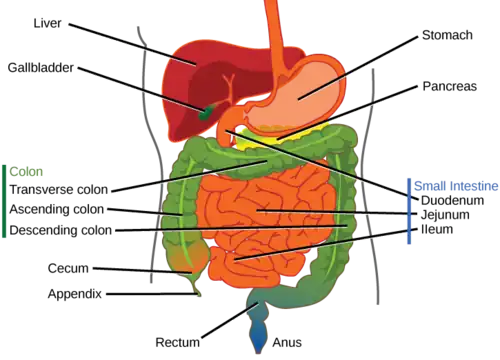

A bowel resection or enterectomy (enter- + -ectomy) is a surgical procedure in which a part of an intestine (bowel) is removed, from either the small intestine or large intestine. Often the word enterectomy is reserved for the sense of small bowel resection, in distinction from colectomy, which covers the sense of large bowel resection. Bowel resection may be performed to treat gastrointestinal cancer, bowel ischemia, necrosis, or obstruction due to scar tissue, volvulus, and hernias. Some patients require ileostomy or colostomy after this procedure as alternative means of excretion.[1] Complications of the procedure may include anastomotic leak or dehiscence, hernias, or adhesions causing partial or complete bowel obstruction. Depending on which part and how much of the intestines are removed, there may be digestive and metabolic challenges afterward, such as short bowel syndrome.

Types of enterectomy are named according to the relevant bowel segment:

| duodenectomy | duodenum | |

| Whipple | duodenum and Pancreas | |

| jejunectomy | jejunum | |

| ileectomy | ileum | |

| colectomy | colon |

Small bowel resection

Large bowel resection